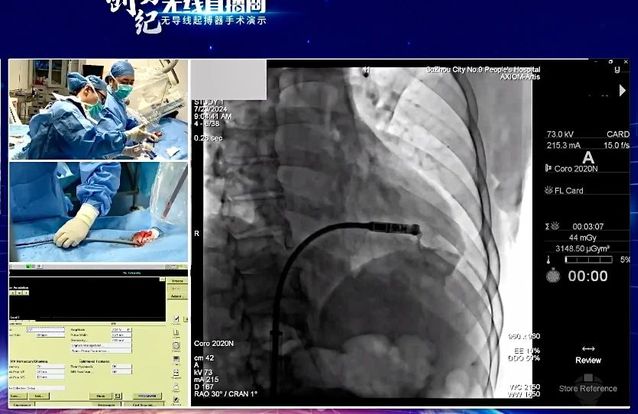

7月24日,“创势纪·无线直播间—苏皖区域无导线起搏器手术演示”在线上举行,苏州九院心血管内科主任吴雁鸣参与手术演示,助力提升区域心血管病防治水平。本次活动由江苏省医学会心血管病学分会副主任委员、苏州市心血管病学分会主任委员、苏州大学附属第一医院心内科主任蒋廷波主持,汇聚了一大批专家教授开展手术演示和线上探讨,通过学术交流积极推动苏皖地区心血管病防治水平的进一步提高。

早在2021年,苏州九院心血管内科就积极引入和开展无导线心脏起搏器植入术,是我区首家成功独立开展无导线起搏器植入手术的医院。心血管内科主任吴雁鸣是我区首位独立无导线起搏器术者,目前已成功独立植入近30例,受益人群大多为高龄老人,其中年龄最大的患者接受手术时已经103岁。

无导线起搏器,代表心脏起搏领域**技术。无导线起搏器(Micra),俗称胶囊起搏器,是目前世界上最小最轻的起搏器,直径6.7mm,长度25.9mm,重量仅1.75g,是国际前沿的先进起搏技术。虽然小,但其电池续航能力强,工作寿命长达12年,植入后还可以接受1.5T/3.0T核磁共振检查。患者无切口、无伤疤、无凸起、无束缚,几乎感觉不到它的存在,是看不见的起搏器,就像默默守护心律失常患者心脏健康的“隐性保镖”。